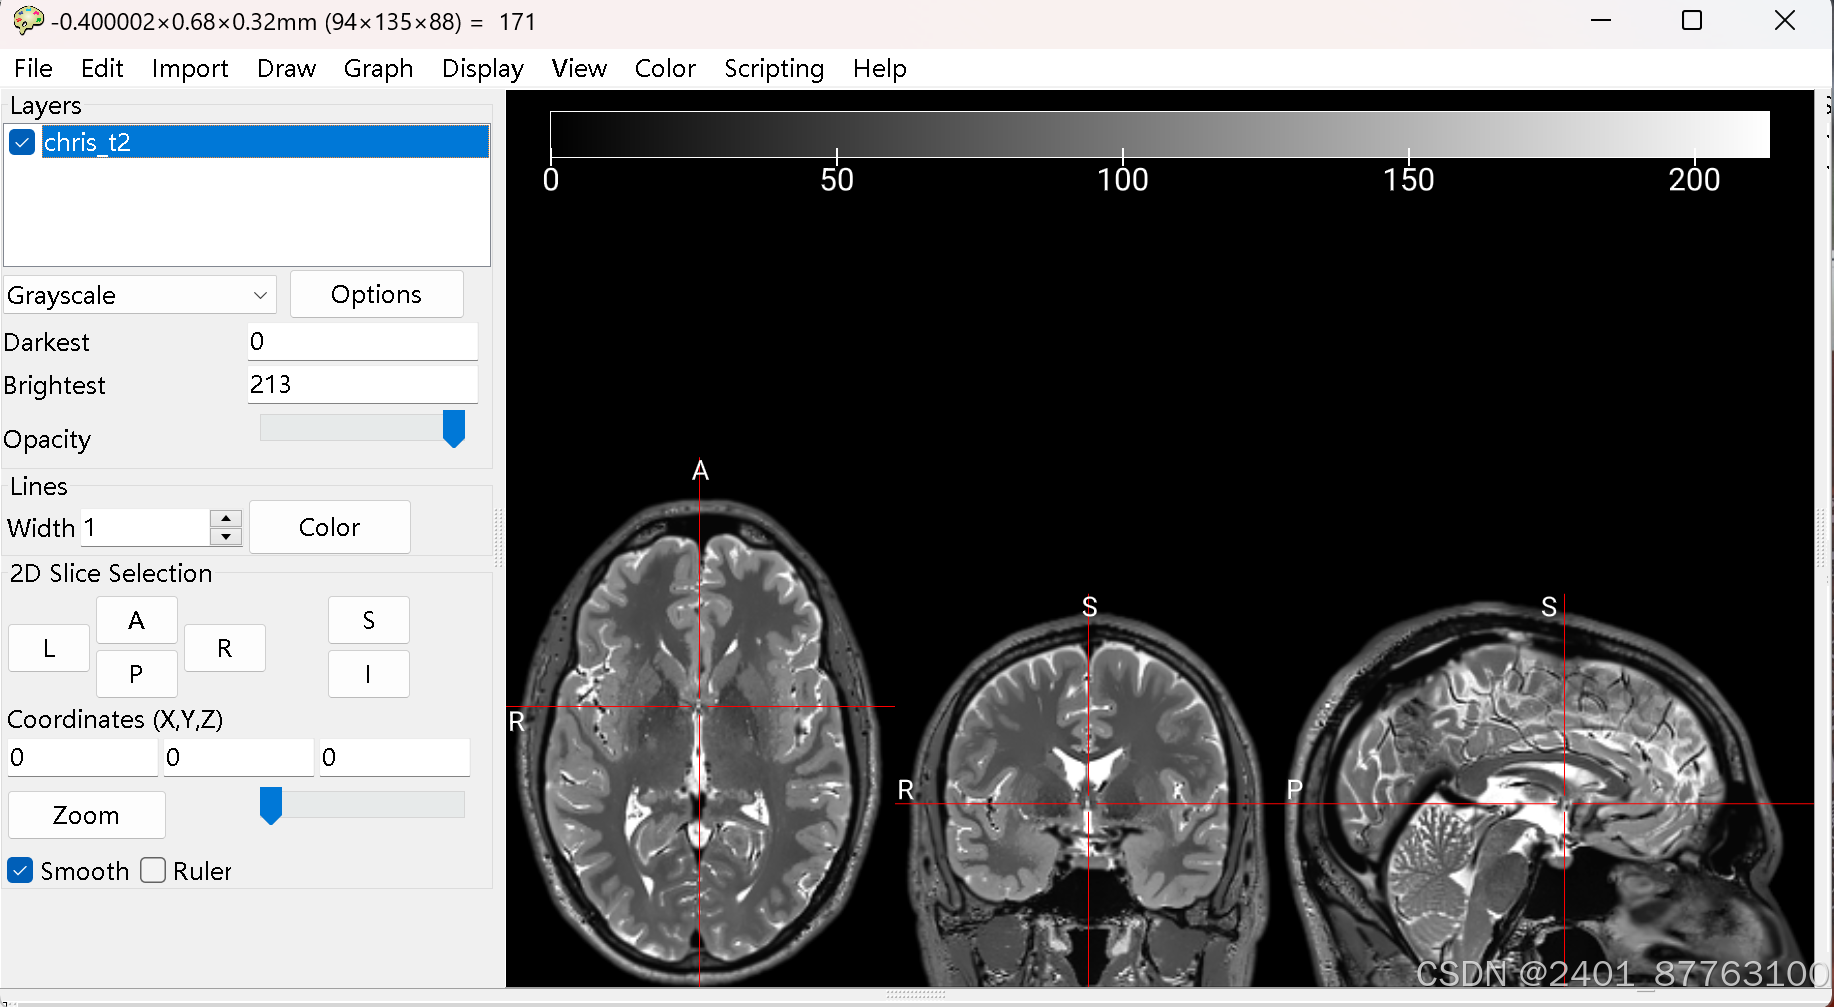

首先利用MRICRO,将DICOM图像转换为NII格式。打开软件----点击import

点击DICOM to NIFTI